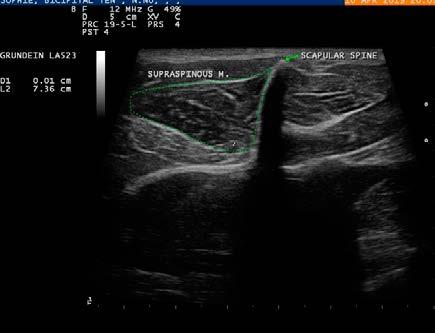

MINERALIZAREA TENDONULUI MUȘCHIULUI SUPRASPINOS LA CÂINEASPECTE ECOGRAFICE ȘI RADIOLOGICE: PREZENTARE DE CAZ

MINERALIZED SUPRASPINATUS TENDON IN DOGS - ULTRASOUND AND RADIOLOGICAL ASPECTS: CASE REPORT Andreea Istrate, R. Constantinescu, Alexandra Peteoacă, A. Tănase